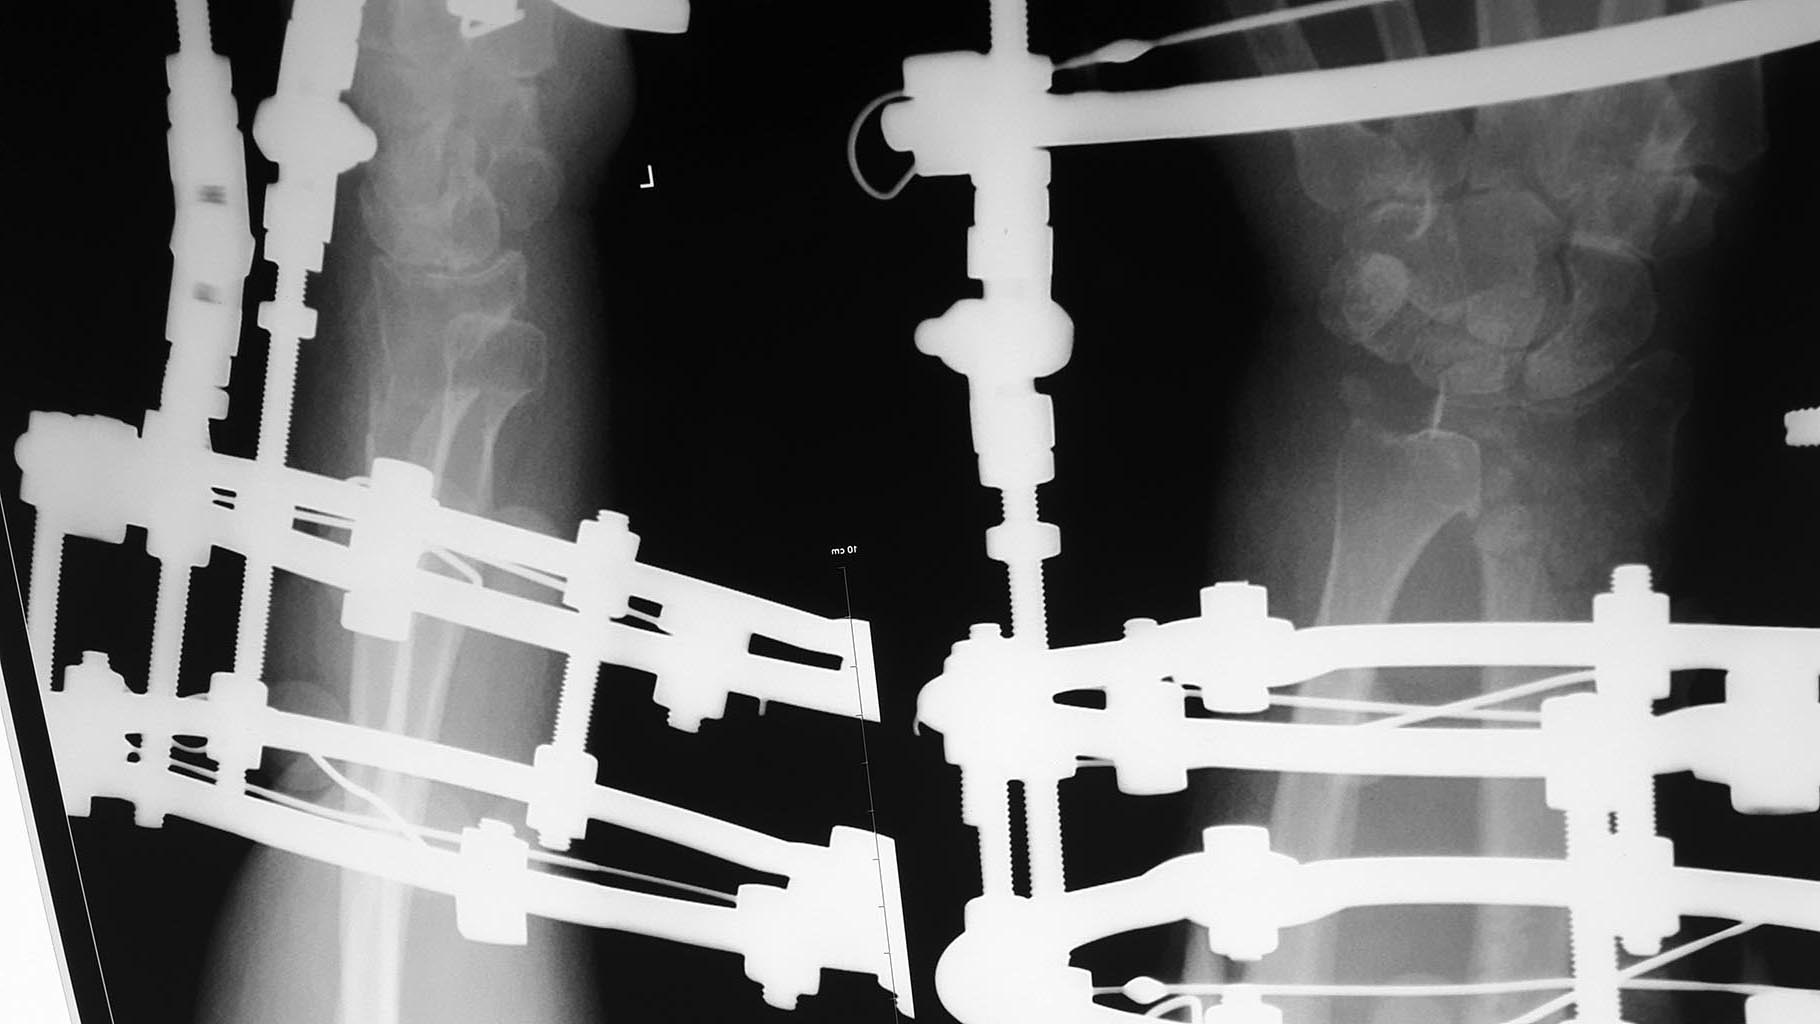

Пациентка 60 лет, 2 мес назад перелом дистального эпиметафиза лучевой кости, шиловидного отростка, Наложен АВФ.

По разным причинам продолжила лечение у хирурга, который проводил дистракцию. Сожалею, первичные снимки предоставить не могу. Рентген при поступлении и после "сброса" дистракции. Сейчас думаем, что с этим делать,четкого плана пока нет, какие у вас мысли по этому поводу?